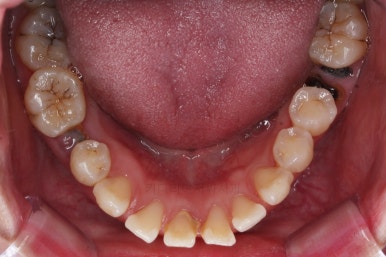

1. 초진

초진 시 입안의 모습입니다.

당장 눈에 띄는 부분은 아래 앞니 사이에 틈새가 있어 치석도 많이 쌓여있는 상황이고요.

윗니-아랫니를 각각 보면 치아가 썩고 부러져 뿌리만 남은 치아가 많이 보입니다.

남은 치아들도 곳곳에 충치가 보이고요.